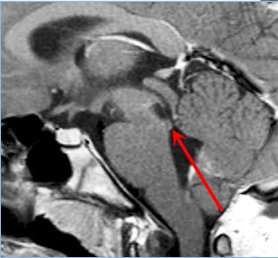

36 岁男性,主诉左侧全身感觉障碍 4 个月,伴轻度偏侧肢体无力。MRI显示延髓下部有一几乎无强化、信号均匀、占位性病变,并向下延伸累及颈髓。患者同意手术,目标为最大限度减瘤并获取确切组织病理学诊断。

术前MRI

幸运的是,手术效果非常好,未出现新的神经功能障碍。组织病理学证实为高级别胶质瘤,WHO III 级,未检出 H3F3A 或 IDH1 突变;无 1p/19q 联合缺失,p53 蛋白无高表达,O6-甲基鸟嘌呤-DNA 甲基转移酶(MGMT)启动子未甲基化。

术后MRI

术后患者接受局部放疗联合替莫唑胺化疗。术后 1 年未见肿瘤进展,生活自理。巴教授对他进行了几年的随访。经过放射治疗和靶向化疗后,他的状况仍然很好。